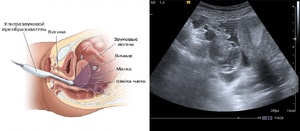

Ультразвуковое исследование матки и ее придатков выполняется несколькими методами:

Трансвагинальное УЗИ. В этом случае датчик вводится во влагалище на глубину 5-7 см, что позволяет детально исследовать матку и придатки. Этот метод считается наиболее информативным, однако его не всегда используют. Трансвагинальное УЗИ противопоказано при наличии кровотечений из половых путей, у девственниц, а также в третьем триместре беременности.

Трансабдоминальное УЗИ. Данный метод осуществляется через брюшную стенку и является более удобным по сравнению с трансвагинальным УЗИ, хотя его информативность несколько ниже. Обычно его применяют для девушек, которые не ведут половую жизнь.

Трансректальное УЗИ. В этом случае датчик вводится в задний проход, что позволяет исследовать матку и придатки через стенку кишечника. Чаще всего этот метод используют для девственниц.

Внутриматочное УЗИ. Датчик вводится непосредственно в полость матки. Этот метод применяется довольно редко и в основном для диагностики изменений в эндометрии и миомы матки.

Как осуществляется трансвагинальное УЗИ яичников? Женщина снимает одежду ниже пояса и укладывается на кушетку. Сканер ультразвукового аппарата вводится во влагалище, что позволяет врачу оценить состояние шейки матки и придатков. При трансректальном УЗИ используется более тонкий датчик. В этом случае женщина должна находиться на левом боку.

Ультразвуковые датчики бывают различных типов, в зависимости от метода исследования. Для УЗИ матки и придатков чаще всего используются трансвагинальные и трансабдоминальные датчики. Трансвагинальный датчик вводится во влагалище и позволяет получить более четкие изображения органов малого таза, так как он находится ближе к исследуемым структурам. Трансабдоминальный датчик применяется для исследования через переднюю брюшную стенку и подходит для более общих оценок состояния органов.